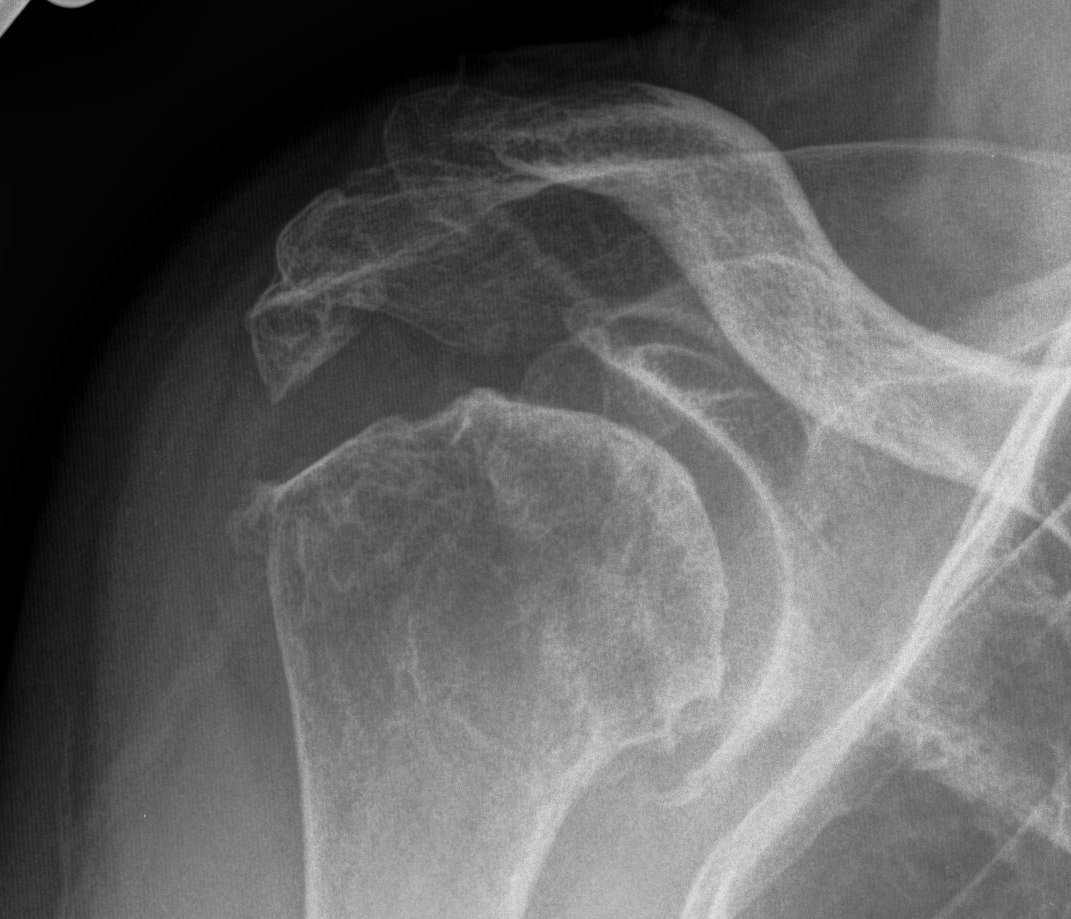

Xray

Typical changes of RA

- regional osteopenia

- marginal erosions and cysts

- humeral head erosions

- medial migration / protrusio

Rheumatoid arthritis with superior and medial wear